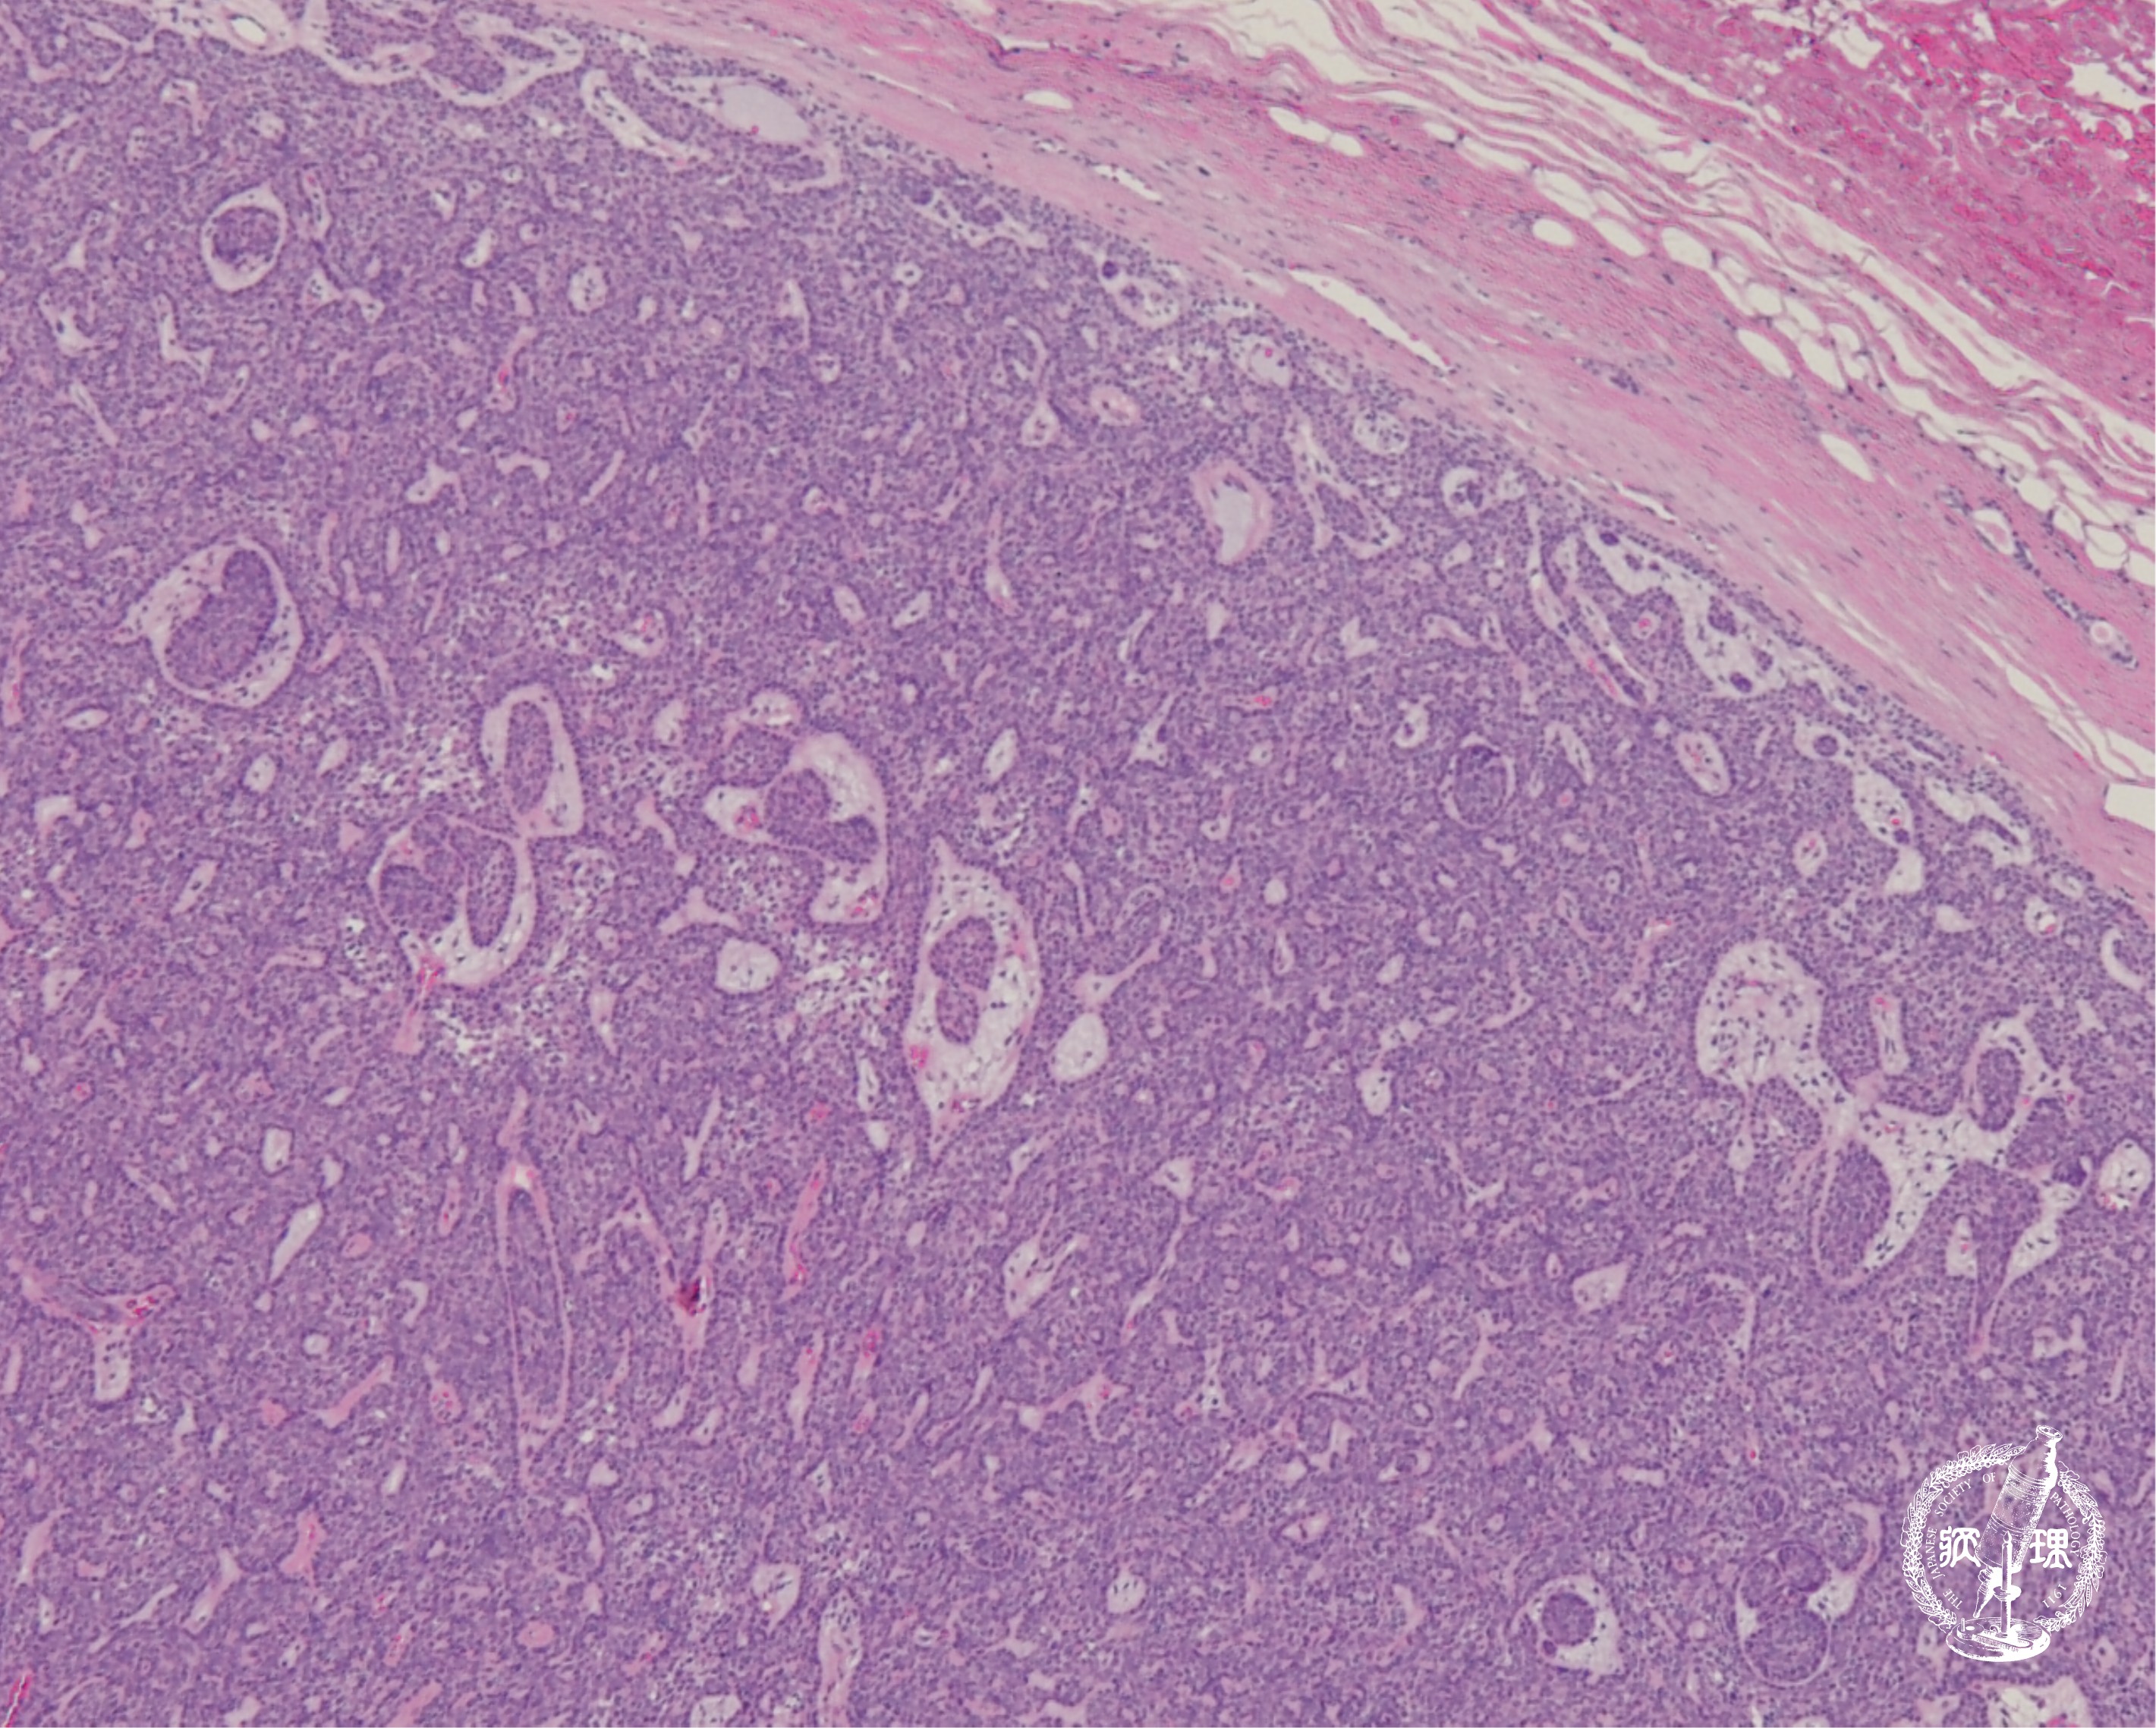

• 唾液腺腫瘍 (基底細胞腺腫)